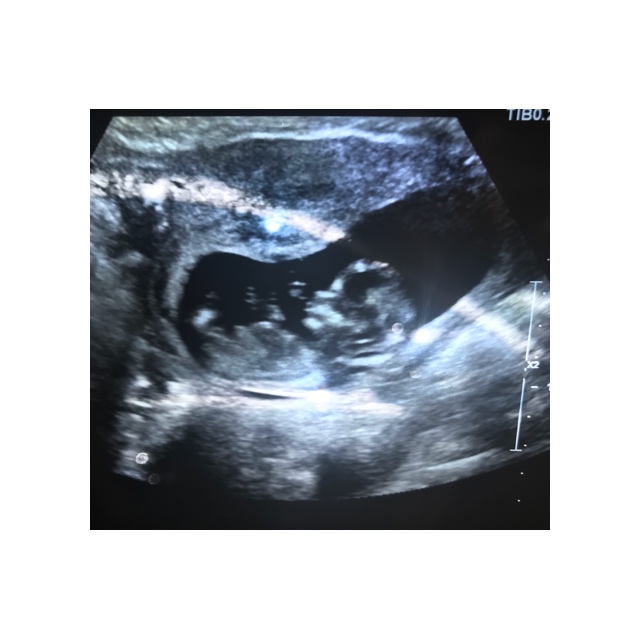

I just had my 12 week scan yesterday. I was 12 weeks 4 days but baby was measuring 13 weeks 1 day.

I didn’t get many good photos & I’m not even sure if the nub is pictured. I’d love any guesses that you might have :)

Attachment 42166Attachment 42167Attachment 42168